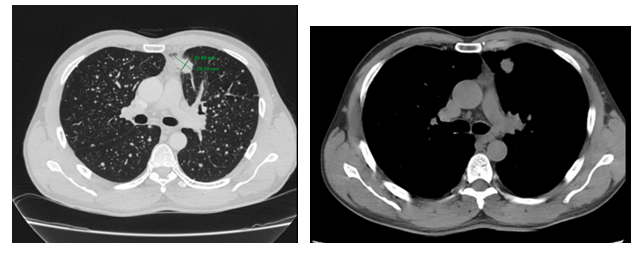

- Chụp cắt lớp vi tính lồng ngực: phim trước điều trị

Hình 1. Trên phim chụp CT lồng ngực ở cửa sổ nhu mô: thùy trên phổi trái có khối đặc tròn bờ tua gai, kích thước: 29 x20mm, kính mờ và dày kẽ xung quanh, lân cận có nốt bán đặc kích thước 29 x 17mm, ngấm thuốc không đồng nhất sau tiêm, nghi ngờ có phần xâm lấn trung thất trước. Nhu mô thùy còn lại và nhu mô phổi phải lan tỏa các nốt đặc tròn to nhỏ không đều, đường kính: 2-8mm.

Hình 2. Cửa sổ trung thất: Vài hạch trung thất cạnh khí, hạch lớn nhất kích thước 14x7mm

- Cắt lớp vi tính lồng ngực:

Sau 3 tháng điều trị đích:

- U nguyên phát và u thứ phát ở cả 2 phổi đều giảm kích thước rất nhiều, không thấy hạch trung thất.

Sau 6 tháng điều trị:

- U nguyên phát chỉ còn kích thước rất nhỏ, u thứ phát 2 bên phổi đã mất hết.